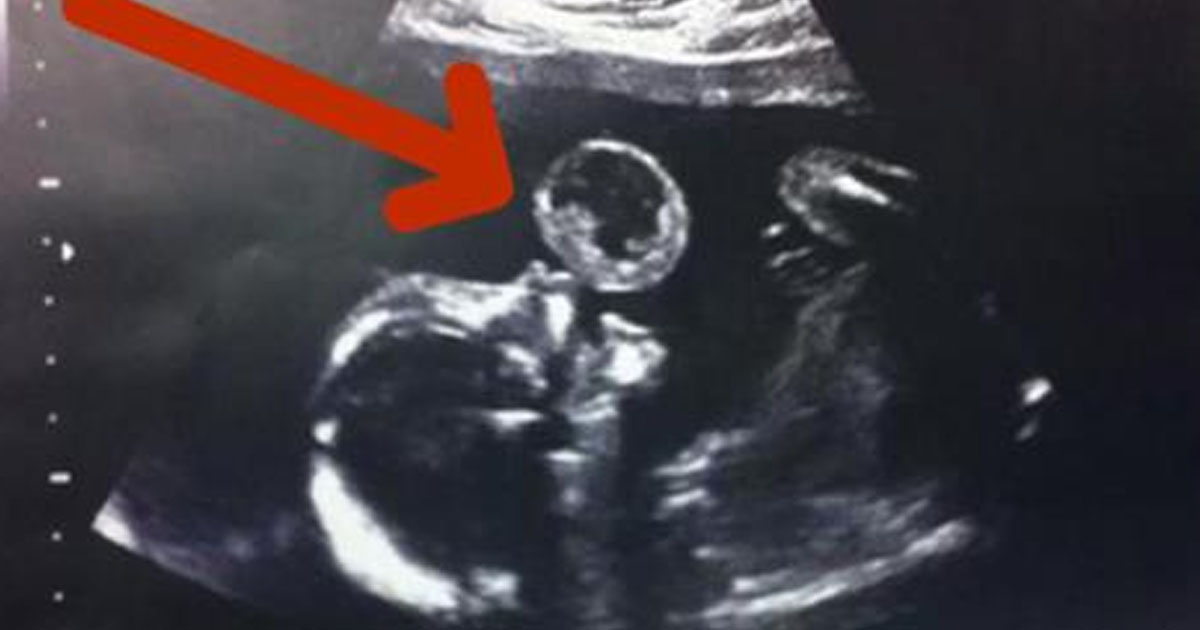

Mom Thinks Her Baby Is Blowing Bubble In Ultrasound, Then Doctors What Is A Bubble Ultrasound An echocardiogram is a test that uses ultrasound to show how your heart muscle and valves are working. What is bubble echocardiogram (bubble echo)? This test does not use radiation. An echocardiogram is done to visualize the heart and its surrounding areas. It is done as part of a medical imaging study called an echocardiogram (echo) that shows the heart's. What Is A Bubble Ultrasound.

Woman Thinks Baby Is Blowing A Bubble In Ultrasound, Then Doctors What Is A Bubble Ultrasound A bubble study is also known as an agitated saline contrast study. An echocardiogram or ‘echo’ is a scan that uses ultrasound (sound waves) to produce pictures of the heart. An echo is a scan that uses ultrasound (sound waves) to produce pictures of the heart this. A bubble contrast echocardiogram (echo) is a painless test which uses ultrasound and. What Is A Bubble Ultrasound.

The ultrasound looks like the baby is blowing a bubble. What the doctor What Is A Bubble Ultrasound It is done as part of a medical imaging study called an echocardiogram (echo) that shows the heart's structure. A bubble study, which is done during an echocardio gram (heart ultrasound), can provide added information about blood flow. An echocardiogram is done to visualize the heart and its surrounding areas. A bubble study is a type of echocardiogram, which is. What Is A Bubble Ultrasound.